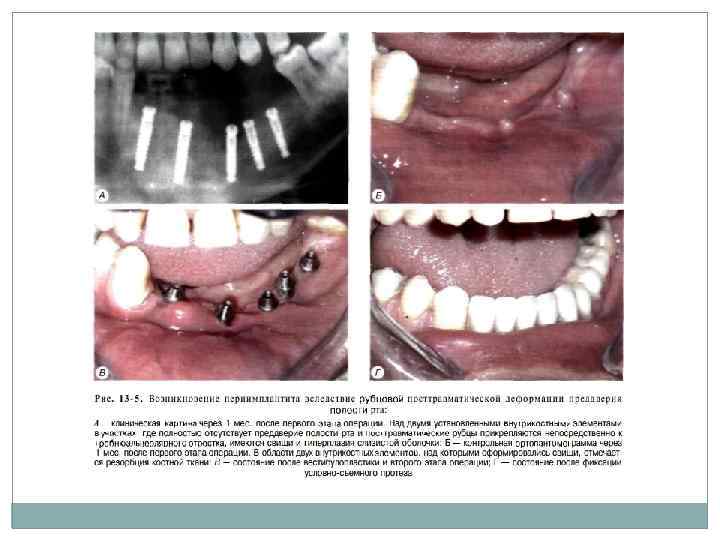

Периимплантит после одноэтапной методики проявляется: болезненностью при надавливании на имплантат; гиперемией и отеком слизистой оболочки, окружающей выступающую в полость рта часть имплантата; отсутствием подвижности или незначительной боковой подвижностью им плантата. Рентгенологически определяется очаг резорбции на границе раздела имплантат кость или образование костного кармана в области вы хода имплантата из кости (рис. 13 4).

Лечение в данном случае сводится к следую щим мероприятиям: • удаление налета с выступающей в полость рта части имилантата. Для этих целей можно ис пользовать скелер, но только с пластиковыми кюретами. а также струйную обработку (на пример, при помощи установки Prophy Jet) стерильным раствором бикарбоната натрия (соды); • детоксикация поверхности имптантата рас твором лимонной кислоты в течение 1 мин; • обработка десневой манжетки антибактери альными гелями; • медикаментозная противовоспалительная терапия (линкомицин. аспирин, метронидазол в обычной дозировке); • гигиенический уход, который подразумевает полоскание полости рта растворами антисептиков и использование зубных наст, содержа щих хлоргексидин; После купирования воспалительных явлений необходимо устранить анатомическую причину (если таковая имеется), например, провестибулопластику или иссечь рубцы преддверия полости рта (рис. 13 5).

Если в результате проведенного лечения ку пировать воспалительные явления не удалось или через некоторое время наблюдается рецидив периимплантита, показано удаление импланта та и ревизия костного ложа. Кроме того, следу ет учитывать, что лечению при использовании одноэтаиной методики подлежат только первые два класса периимплантита. При III и IV классах показано удаление одноэтапных имплантатов и ревизия костного ложа. Реимплантацию можно провести через 2 3 нед. на расстоянии 2 3 мм от места первона чального вмешательства (если позволяют ана томические условия) или через 1 1. 5 мес. если можно установить в том же участке внутрикостный элемент двухэтапного имплантата большего диаметра, или через 6 мес. применив имплантат аналогичный по форме и размерам удаленному.